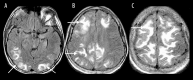

Toxic leukoencephalopathy results from damage to the white matter caused by various toxins. It manifests itself as white matter signal abnormalities with or without the presence of restricted diffusion. These changes are often reversible if the insulting agent is removed early, with the exception of posthypoxic leukoencephalopathy that can manifest itself 1-2 weeks after the initial insult. However, many other potential causes of white matter signal abnormalities can mimic the changes of toxic leukoencephalopathy. Thus, familiarity with the causes, clinical presentation and particularly imaging findings of toxic leukoencephalopathy is critical for early treatment and improved prognosis. The purpose of this pictorial essay is to familiarize the reader with the various causes of toxic leukoencephalopathy along with its differential diagnoses and mimics.